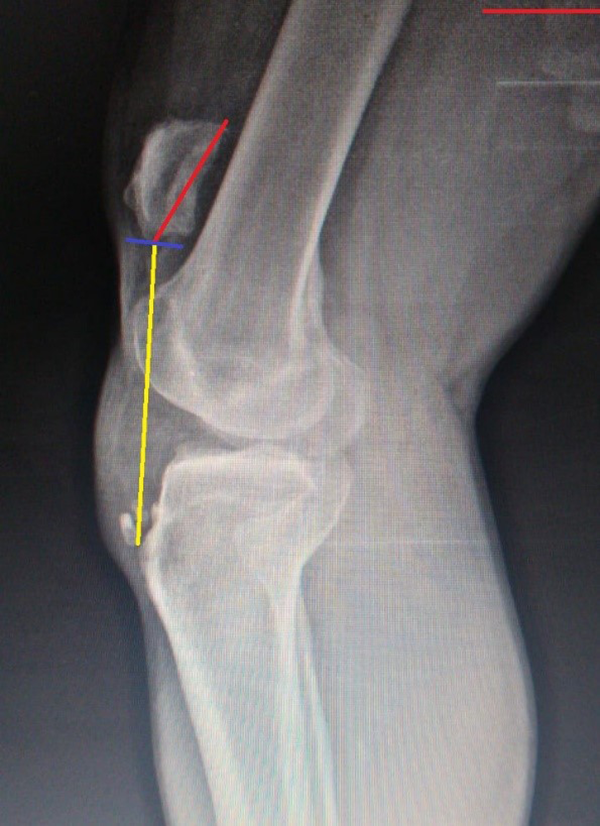

Al examen radiológico se evidencia migración de 6 cm de la rótula hacia proximal y aumento del índice Insall-Salvati: 2 (fig. 3). La RM informa avulsión del polo distal de la rótula. El paciente asistió nuevamente a nuestro servicio con seis meses de evolución.

Figura 3: Radiografía prequirúrgica. Insall-Salvati: 2.